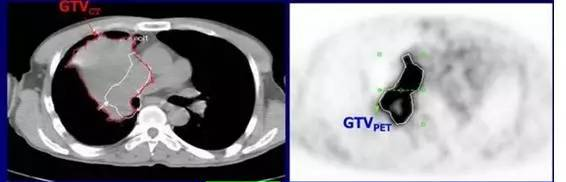

4、指導(dǎo)放療靶區(qū)勾畫

腫瘤靶區(qū)勾畫是放療的關(guān)鍵步驟之一,CT是目前放療定位的主要方法,但對肺癌合并阻塞性肺炎、肺不張和胸腔積液者應(yīng)用CT確定腫瘤邊界有一定困難。PET/CT同時提供有關(guān)腫瘤的解剖和功能信息,為腫瘤靶區(qū)的勾畫提供更加全面和準(zhǔn)確的信息, 在一定程度上減少了不同觀察者靶區(qū)勾畫的差異,提高靶區(qū)勾畫的準(zhǔn)確性和一致性。Erdi等發(fā)現(xiàn)PET/CT的應(yīng)用使患者的計劃靶體積由于包括了CT未發(fā)現(xiàn)的轉(zhuǎn)移病灶而提高了19%,因避開肺不張等原因而下降了18%。